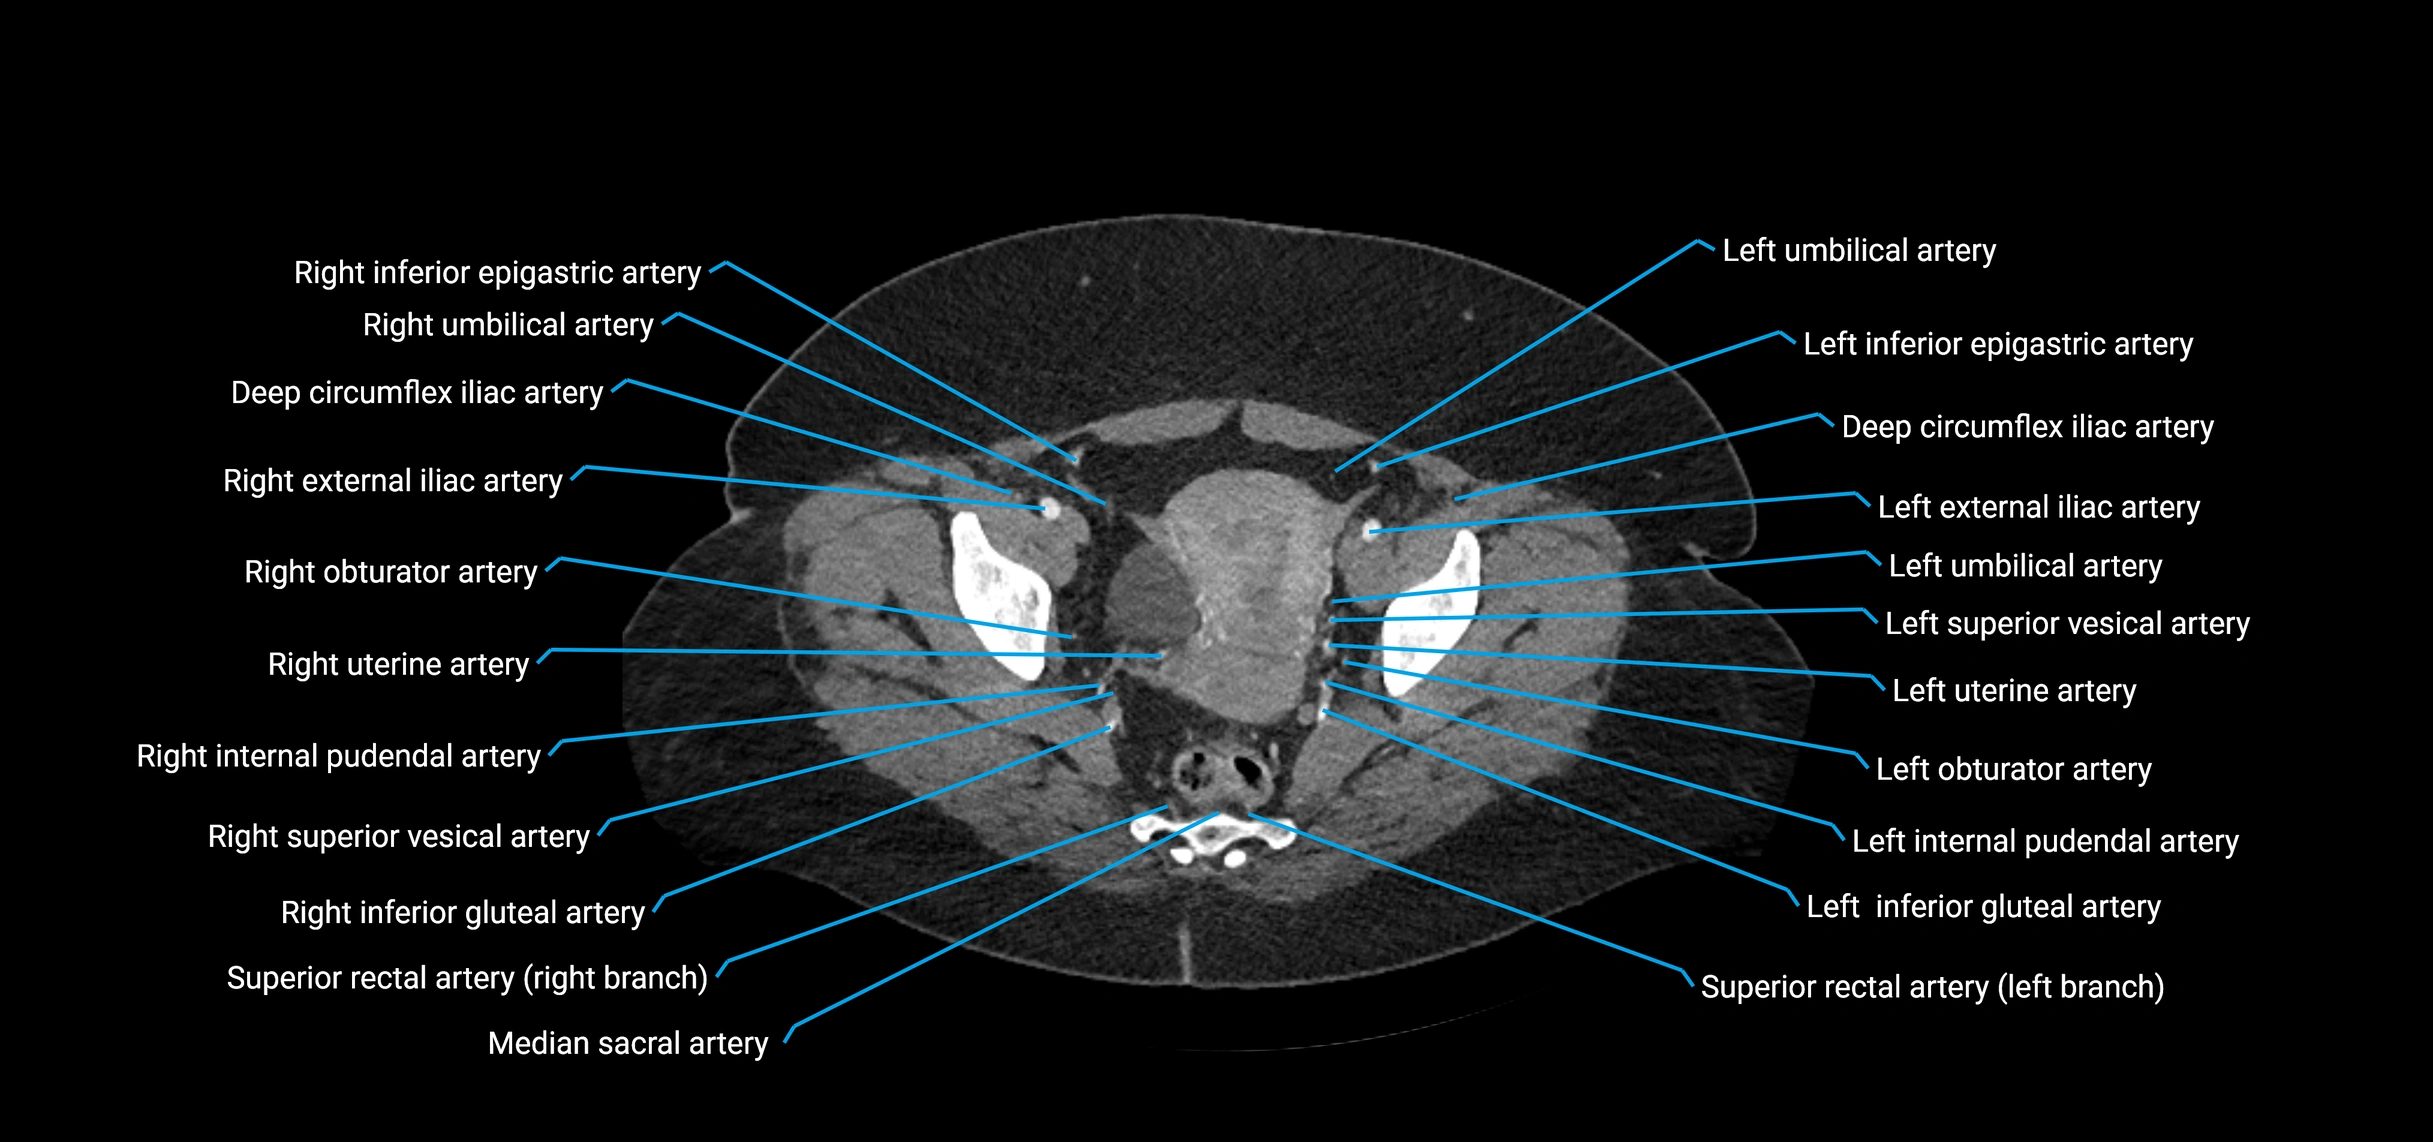

The abdominal aorta is the continuation of the thoracic aorta, beginning at the level of the aortic hiatus of the diaphragm (T12 vertebra) and terminating at the level of the L4 vertebra where it bifurcates into the right and left common iliac arteries. It lies slightly to the left of the midline and courses anterior to the vertebral bodies, surrounded by the retroperitoneal structures of the abdomen.

The abdominal aorta gives off numerous visceral and parietal branches, supplying the abdominal organs, pelvic structures, and lower limbs. It is the main conduit of oxygenated blood from the heart to the abdomen and lower body. The aorta is clinically significant as the common site of aneurysm, dissection, atherosclerosis, and traumatic injury.

Branches

• Unpaired visceral branches: celiac trunk, superior mesenteric artery (SMA), inferior mesenteric artery (IMA)

• Paired visceral branches: middle suprarenal arteries, renal arteries, gonadal arteries (testicular or ovarian)

• Parietal branches: inferior phrenic arteries, lumbar arteries, median sacral artery

• Terminal branches: right and left common iliac arteries

CT Appearance

Contrast-enhanced CT (CTA):

• Gold standard for abdominal aortic imaging

• Provides excellent detail of lumen, wall, aneurysm, thrombus, and branch vessels

• Multiplanar and 3D reconstructions help in aneurysm measurement, stent graft planning, and dissection evaluation

• Detects acute rupture, traumatic injury, or occlusion with high sensitivity